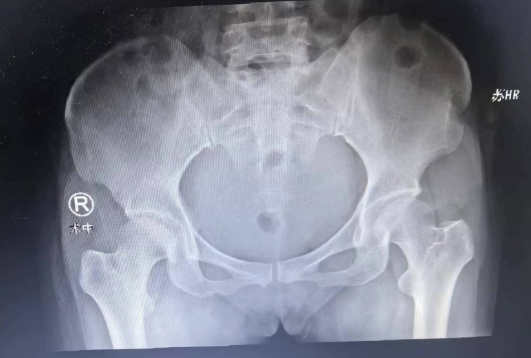

术前检查

郑大伟主任是一位在手外科领域有着丰富经验的专家。他详细分析了患者的病情,制定了一套全面的治疗方案。手术中发现,肿瘤已经侵犯了指骨近节,这是一个非常棘手的问题。但是,郑主任凭借其精湛的医术,术中成功地去除了肿瘤组织,并且进行了同侧髂骨植骨术,以恢复指骨的功能。

因肿瘤侵犯指骨近节,术中去除肿瘤组织后,予取同侧髂骨植骨术